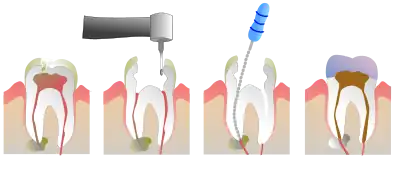

Root canal treatment (also known as endodontic therapy, endodontic treatment, or root canal therapy) is a treatment sequence for the infected pulp of a tooth which is intended to result in the elimination of infection and the protection of the decontaminated tooth from future microbial invasion.[1] Root canals, and their associated pulp chamber, are the physical hollows within a tooth that are naturally inhabited by nerve tissue, blood vessels and other cellular entities. Together, these items constitute the dental pulp.[2]

Endodontic therapy involves the removal of these structures, disinfection and the subsequent shaping, cleaning, and decontamination of the hollows with small files and irrigating solutions, and the obturation (filling) of the decontaminated canals. Filling of the cleaned and decontaminated canals is done with an inert filling such as gutta-percha and typically a zinc oxide eugenol-based cement.[3] Epoxy resin is employed to bind gutta-percha in some root canal procedures.[4] Another option is to use an antiseptic filling material containing paraformaldehyde like N2.[5] Endodontics includes both primary and secondary endodontic treatments as well as periradicular surgery which is generally used for teeth that still have potential for salvage.[6][7]